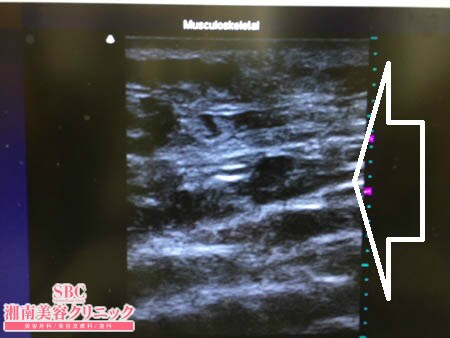

いつものように3Dタッチビュー(超音波)で

皮下脂肪層を評価してみましょう。